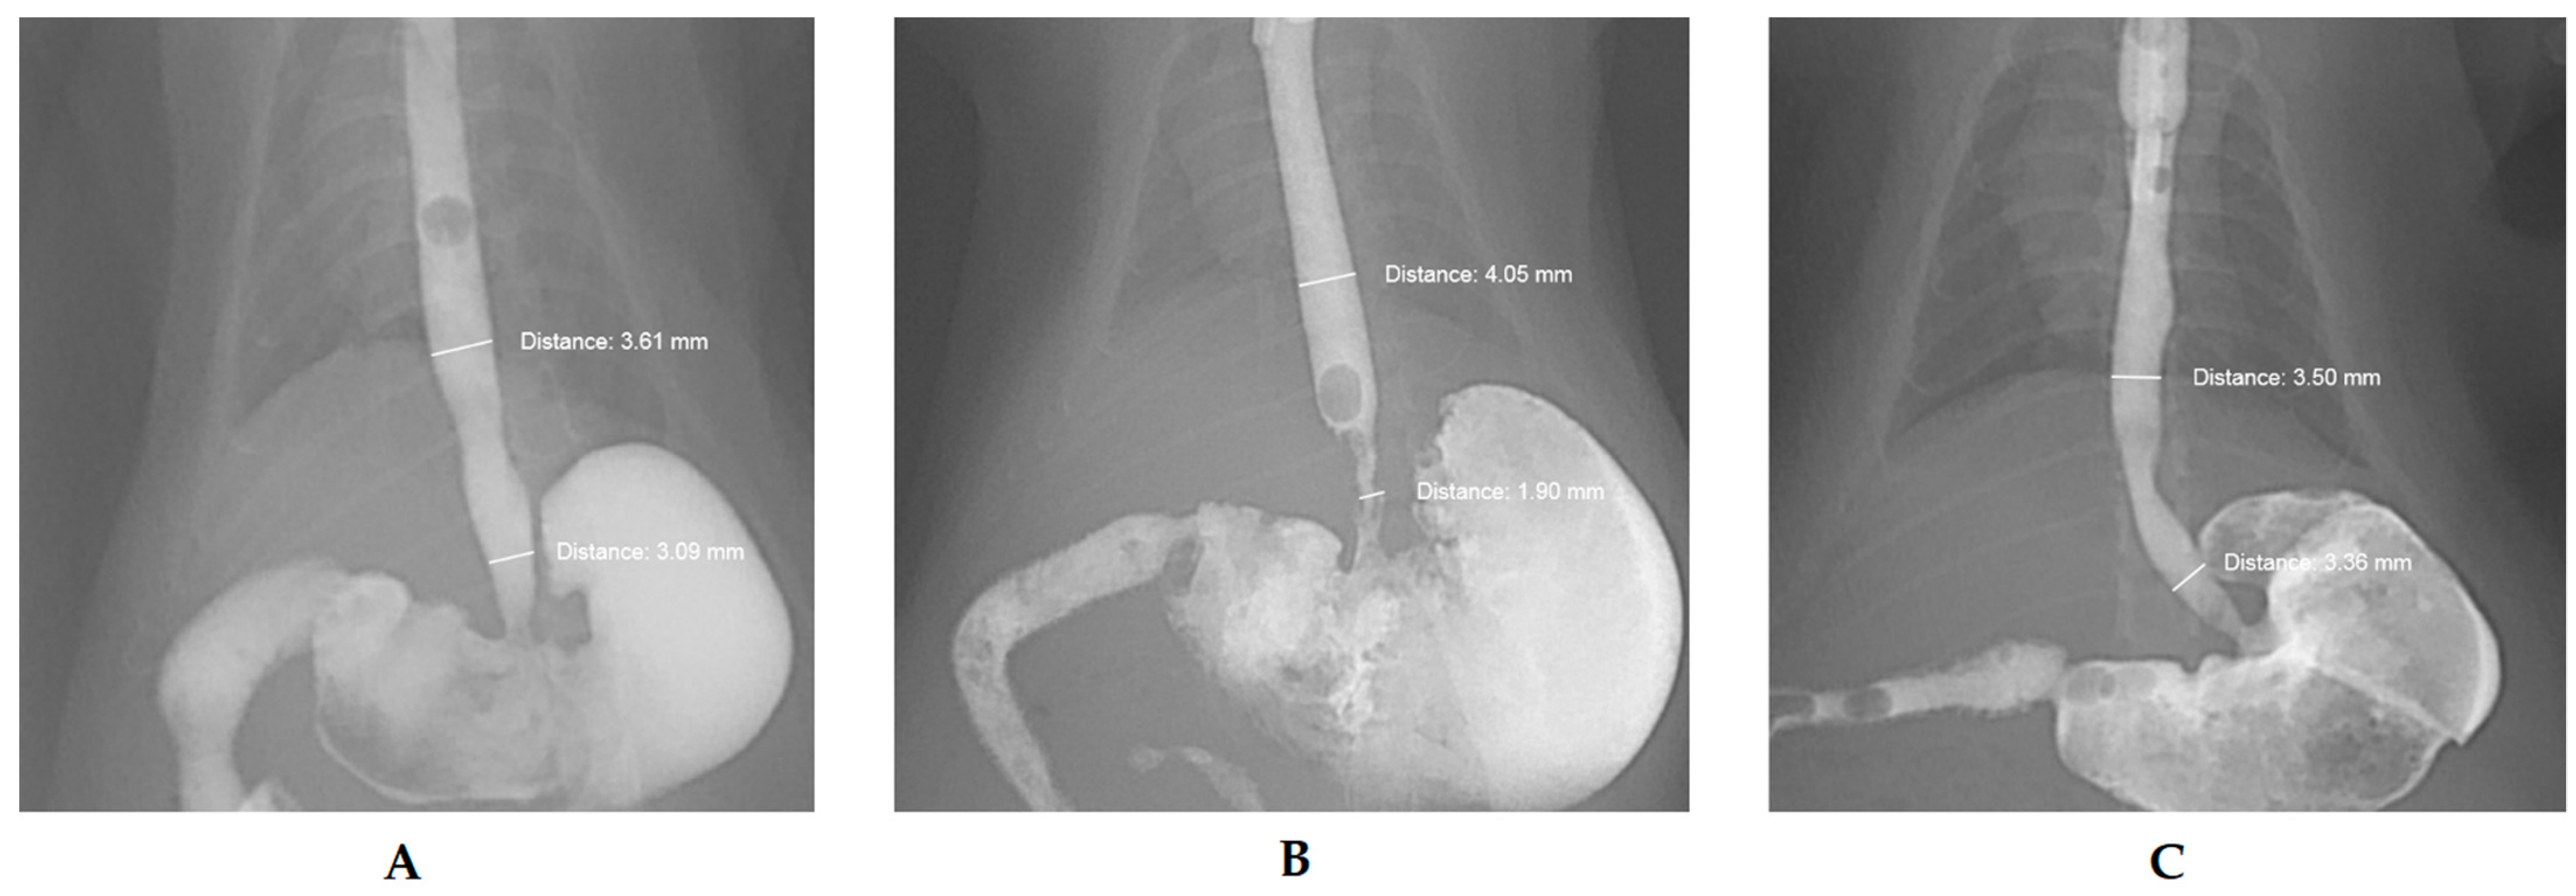

2.4. Fluoroscopic Esophagogram

3.1. Effect of the Drug on Esophageal Stenosis